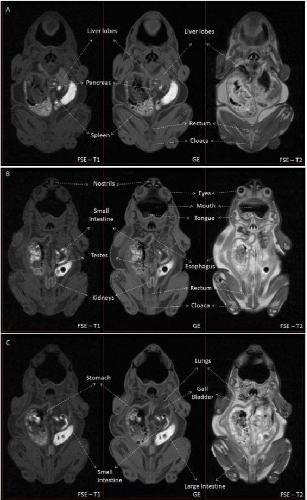

Sex Determination in Two Species of Anuran Amphibians by Magnetic Resonance Imaging and Ultrasound Techniques., Ruiz-Fernández MJ, Jiménez S, Fernández-Valle E, García-Real MI, Castejón D, Moreno N, Ardiaca M, Montesinos A, Ariza S, González-Soriano J., Animals (Basel). November 18, 2020; 10 (11):